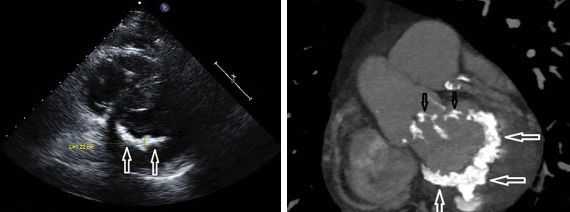

Другой важный инструментальный метод диагностики — эхокардиография (Эхо-КГ) . Эхо-КГ — это безболезненное ультразвуковое исследование, которое позволяет исследовать работу сердца в реальном времени. Эхокардиография покажет уменьшение эластичности клапана, его повреждение, размер отверстия митрального клапана и расстояние между его створками. Также при исследовании можно увидеть разрыв папиллярной мышцы и провисание клапанных створок в полость левого предсердия [4] [8] [9] .

При разрыве поврежденной хорды часть створки клапана западает в предсердие, что обычно вызывает тяжелую регургитацию.